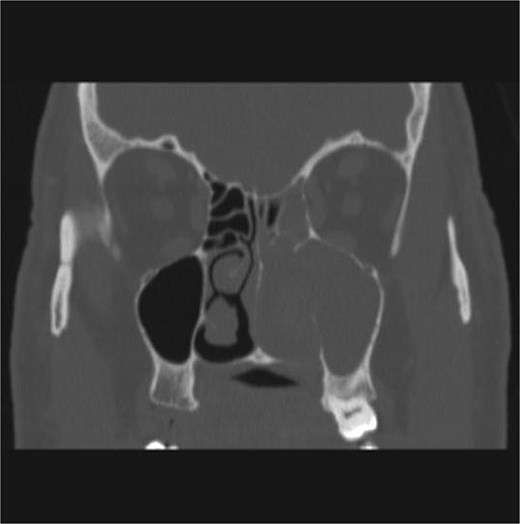

CT showed a heterogeneously enhancing mass completely occluding the left nasal cavity, left ethmoidal, maxillary and frontal sinuses, extending to left pterygopalatine fossa. It is associated with bony erosion of the posterior nasal septum and the left medial maxillary wall (Figs 1 and 2). Findings were suggestive of inverted papilloma vs sinonasal malignancy. Therefore, biopsy was recommended.

Coronal section of CT paranasal sinus with contrast bone window showing the bony erosion in the nasal septum and maxillary sinus wall.